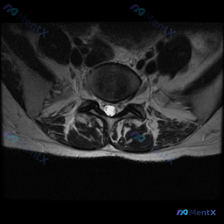

看到一个挺有启发的读片病例,临床预设是椎间盘病变,整理了完整分析思路分享给大家。 病例影像基础信息 这是一张腰椎MRI T1加权轴位图像,对应腰椎下段(L4/5或L5/S1椎间盘水平),影像所见如下: 1. 骨性结构:椎体后缘轮廓清晰,椎弓根、椎板及关节突关节结构未见异常;椎体骨髓信号均匀,无局灶性...

拿到这份资料:临床怀疑椎间盘病变,只提供了一张腰椎MRI T2加权轴位图像,我整理了分析思路跟大家分享。 先看这份影像本身的信息 这是腰椎L3/4或L4/5椎间盘水平的轴位片,影像可见: 1. 解剖结构:中央硬膜囊脑脊液信号正常,椎体后缘轮廓清晰,两侧关节突关节间隙对称,黄韧带无明显增厚钙化,椎旁软...

收到一份腰椎MRI单张轴位片,临床怀疑椎间盘病变,整理一下读片思路和分析,和大家交流。 一、影像基本信息 这是一张腰椎MRI T2加权轴位扫描图像,我们逐层拆解结构: 1. 椎体与终板:椎体后缘信号正常,低信号符合皮质骨表现,没有明显骨质破坏、水肿,也没有典型Modic终板炎改变 2. 椎间盘:髓核...